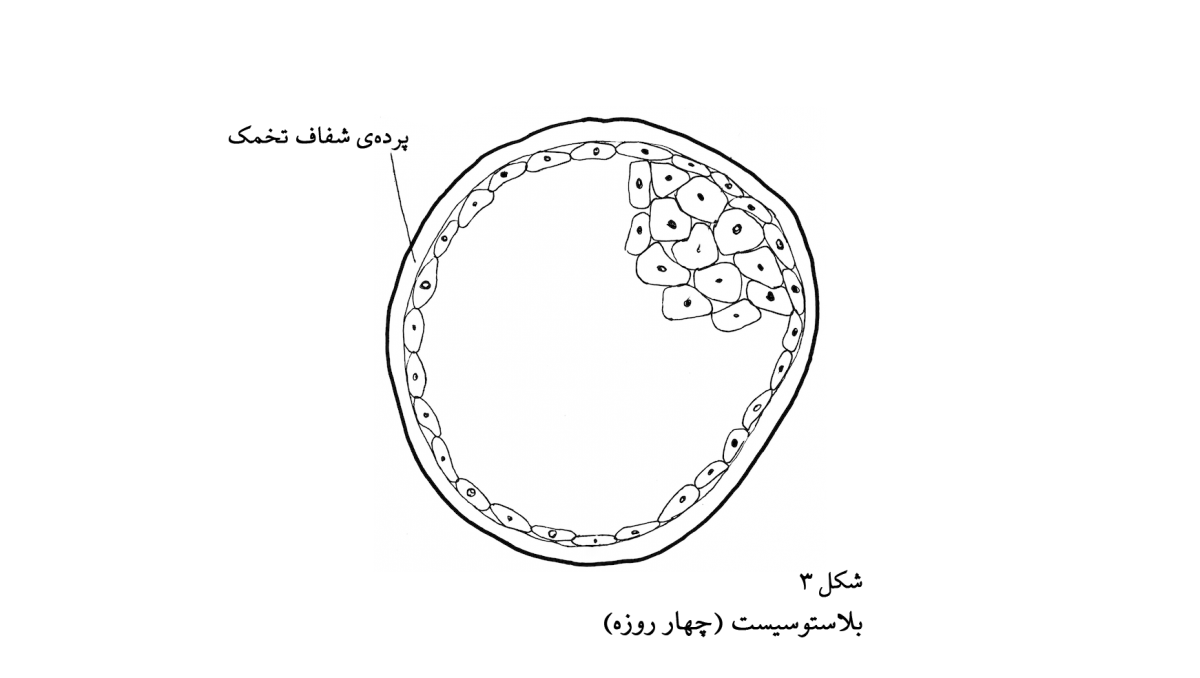

دلایل متقنی وجود دارد که لری به شکل توتهی دو، چهار، هشت، یا شانزده یاختهای وجود ندارد، زیرا توته مجموعهای از چیزها است و نه فردی واحد؛ در نتیجه، او در مراحل ابتداییتر، به شکل یاختهی تخم، نیز وجود ندارد. اما کمی بعدتر چطور، مثلاً در روزهای چهارم، پنجم، یا ششم؟ برای این که بتوانیم در این باره بیاندیشیم، به واقعیتهای بیشتری دربارهی رویانزایی نیاز داریم. خوشهی یاختهها در داخل پردهی شفاف دیوارهی تخمک تقسیم میشود و نمیتواند گسترش زیادی بیابد. در نتیجه، یاختهها رفته رفته کوچکتر میشوند. سپس، تقریباً در روز چهارم پس از لقاح، بیرونیترین لایهی یاختهها (حدود صد یاخته) به هم فشرده میشوند، و سپس طی تحولاتی توته به بلاستوسیست (شکل ۳) تبدیل میشود. سپس در روز پنجم تغییر عمدهی دیگری روی میدهد: بلاستوسیست از داخل پردهی شفاف دیوارهی تخمک خارج میشود. بلاستوسیست، که اینک از آن کیسهی محدودکننده خارج شده است، بلافاصله شروع به رشد میکند و تودهی یاختههای درونی شروع به متمایز شدن میکنند. در روز ششم، بلاستوسیست به انتهای مسیر خود در لولهی رحم میرسد و در دهانهی رحم جای میگیرد.

حال، با در نظر گرفتن این اطلاعات، آیا میتوان گفت که یکپارچگیِ بلاستوسیت آن اندازه هست که آن را یک موجود زنده در نظر بگیریم و بگوییم این نخستین تجسمِ لری است؟ بیشک، بلاستوسیست وحدتی بیش از کیسهی تیلهها دارد، اما تمام ویژگیهای یک موجود زنده را ندارد: هنوز رشد نمیکند (به علت وجود پردهی شفاف تخمک)، و راهی برای حفظ ثبات خود ندارد. با این حال، حتی اگر مسئلهی وحدت را کنار بگذاریم، دلایلی دیگری وجود دارند که بلاستوسیست را سرآغاز لری ندانیم. بلاستوسیست حاوی تمام محتویات رویان و ساختارهای حمایتیِ آن است. در واقع، ۸۵ درصد بلاستوسیست به ساختارهای حمایتی و ۱۵ درصد آن به جنین تبدیل خواهد شد. بلاستوسیست در روز چهارم مجموعهای از جنین و ساختارهای حمایتی آن است (شکل ۴) و صرفاً تداومِ جنین نیست. اگر بتوان منشأ لری، پسر پنج سالهی شما را صرفاً در جنین بالغ نه ماهه، هشت ماهه، شش ماهه، و .... جست، و منشأ این جنین بالغ در کلیت بلاستوسیست نباشد، در این صورت کلیت بلاستوسیست منشأ لری نیست.